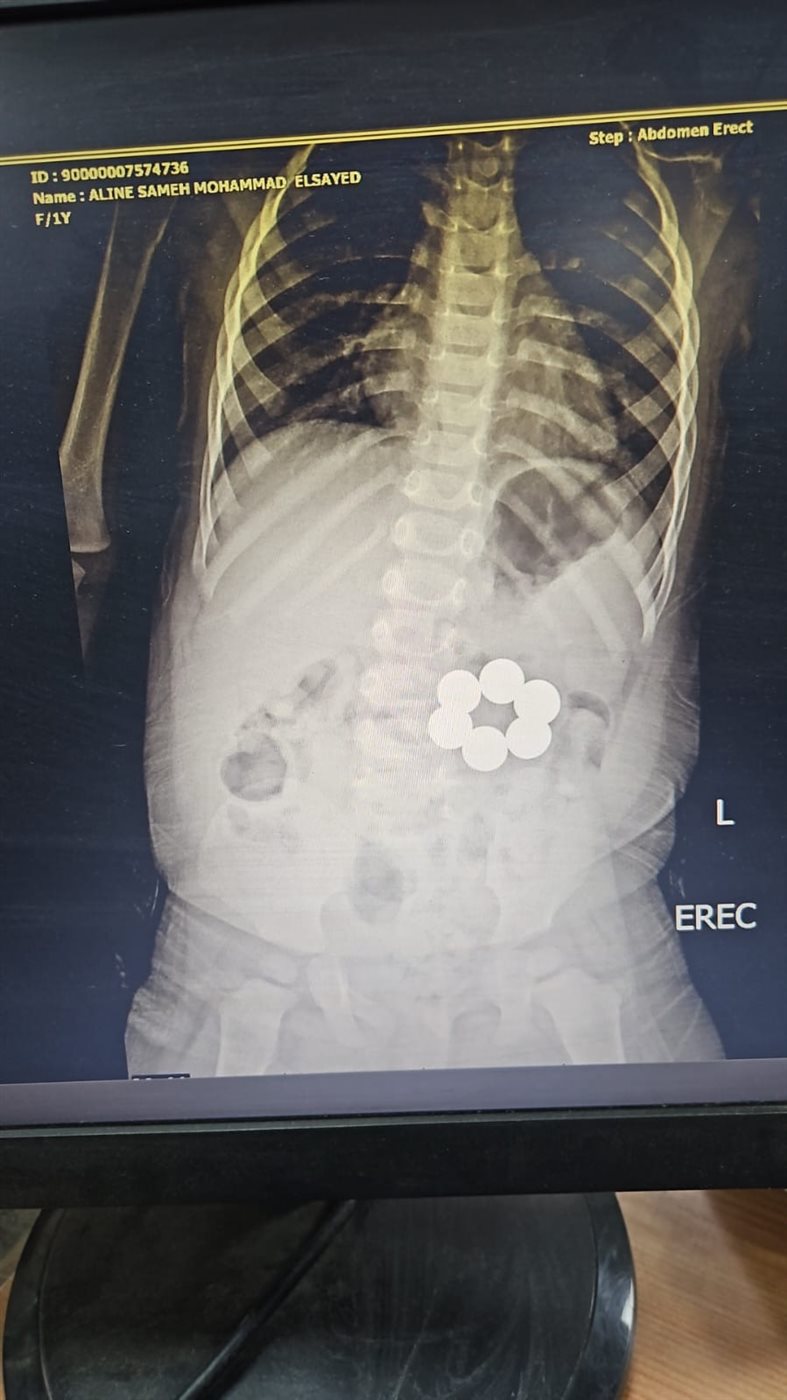

وتعود تفاصيل الواقعة إلى اليوم الثلاثاء، الموافق 7 أبريل 2026، حين استقبل المستشفى الطفل وهو يعاني من أعراض مقلقة للغاية نتيجة ابتلاعه لـ «6 قطع مغناطيس» ذات قوة جذب عالية، مما شكل تهديداً مباشراً ومميتاً لحياته وحالة من الذعر لدى أسرته في مطلع ربيع هذا العام.

وكشفت الفحوصات الدقيقة والأشعة التشخيصية عن وجود هذه القطع داخل الجهاز الهضمي الصغير للطفل، وهي حالة طبية تصنف بأنها «شديدة الخطورة»؛ نظراً لاحتمالية التصاق القطع ببعضها البعض عبر جدران الأمعاء، مما قد يتسبب في حدوث ثقوب معوية أو انسداد كامل ومضاعفات قد تؤدي إلى الوفاة إذا لم يتم التدخل في التوقيت المناسب.

ونجح الفريق في استخراج كافة «القطع المغناطيسية الست» بدقة متناهية وفي وقت قياسي، دون تسجيل أي مضاعفات تذكر أثناء أو بعد الإجراء الطبي.

وأكدت التقارير الطبية الصادرة اليوم 7 أبريل أن الجهاز الهضمي للطفل ظل سليماً تماماً، وخرج الصغير في حالة مستقرة ليعود إلى حضن أسرته بصحة جيدة بفضل الله ثم كفاءة أطباء المنصورة.